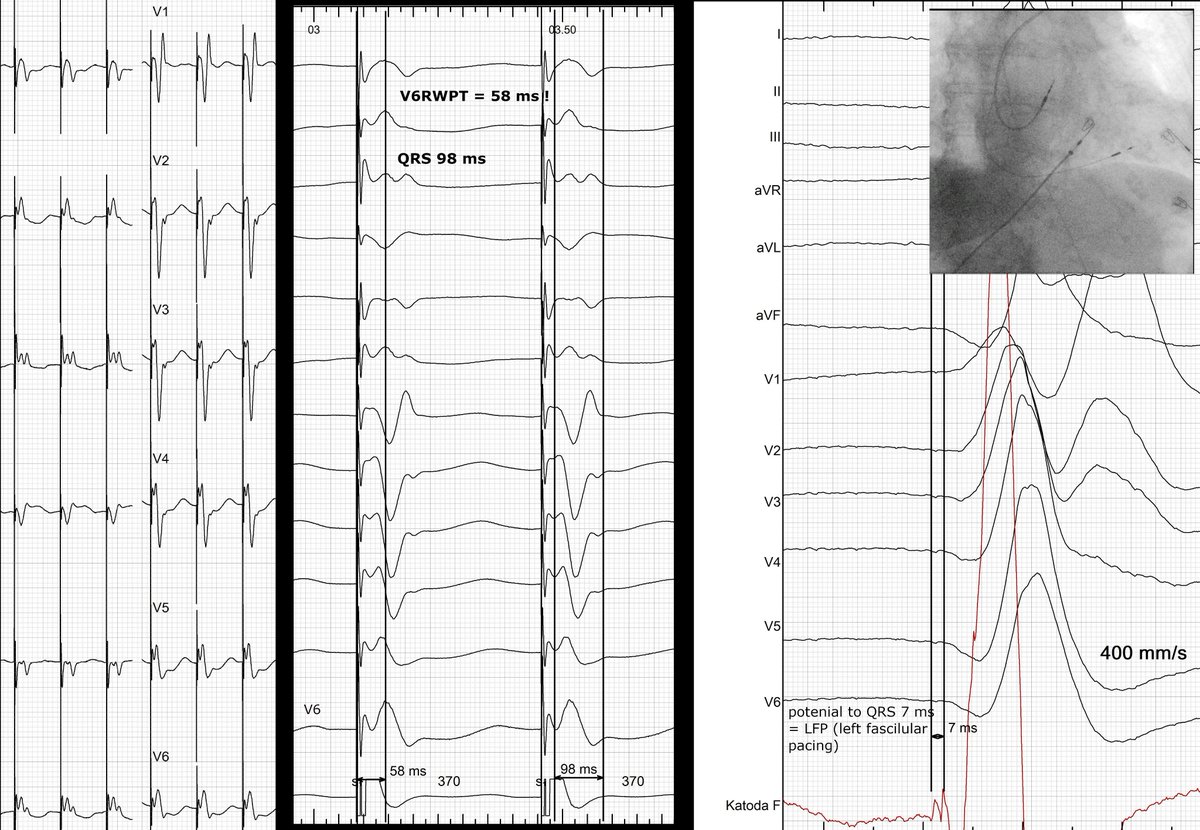

The “magic” moment confirming LBBPcapture by @Marek_Jastrz_EP #PPS6 @drpmoskal